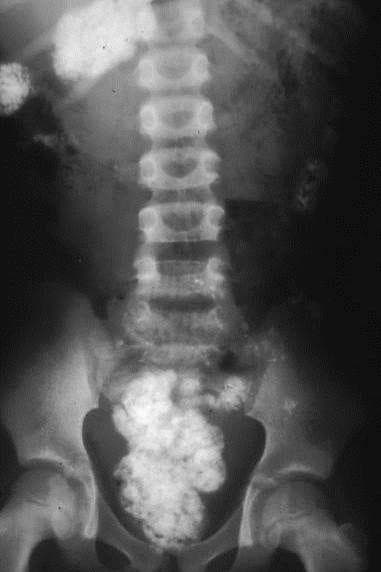

From gppaedstips.blogspot.com

Paediatrics for Primary Care (and anyone else) Better FOAM are you Will Egg Cause Cough Allergies can cause mucus overproduction and the resulting congestion or breathing problems, along with other symptoms. Coughing is your body's natural defense when it detects irritants within your respiratory system. What causes an egg allergy? Skin inflammation or hives — the most common egg allergy reaction. In the case of egg allergies, both egg yolks and egg whites contain proteins. Will Egg Cause Cough.